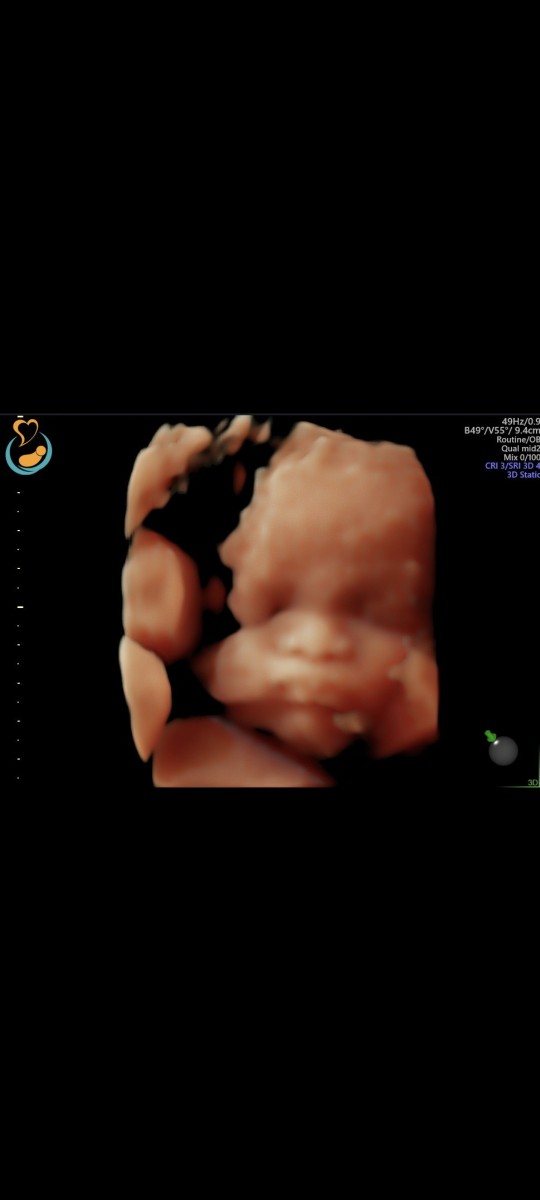

numpang tanyaa kandungan saya udah 5 bulan pas bulan kemaren sampe minggu kemaren gerakan janin lancar dan tiba2 kok sekarang gak berasa ya pergerakan janin saya . jujur saya khawatir